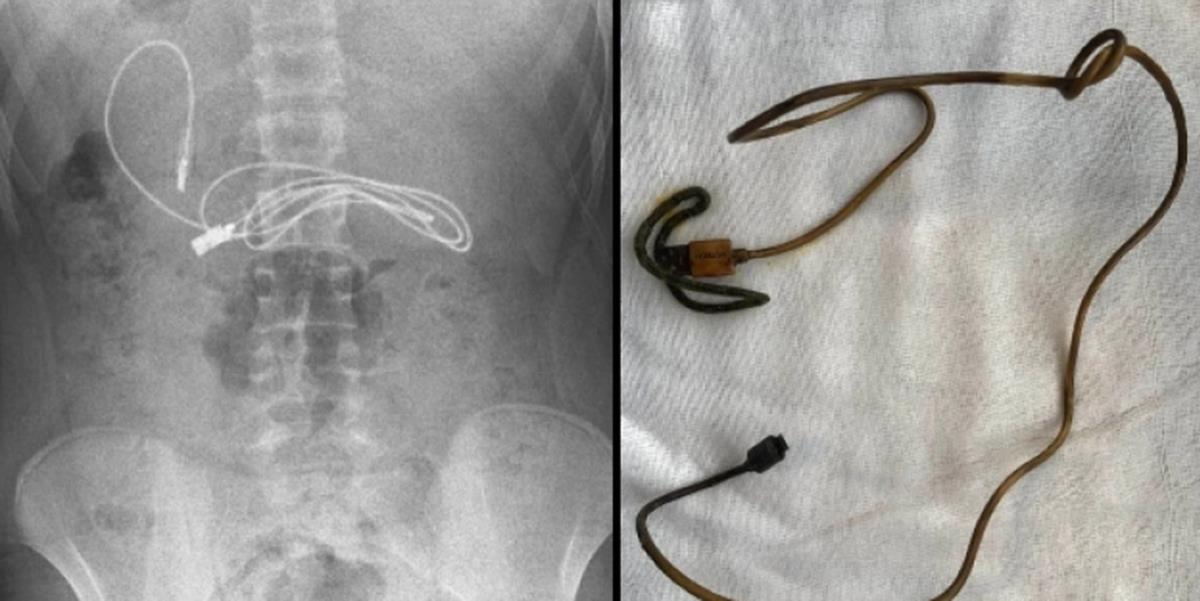

Το αγόρι από τον Ντιγιαρμπακίρ μεταφέρθηκε εσπευσμένα από την οικογένειά του